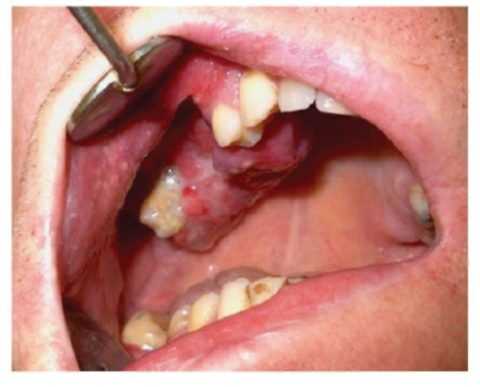

Диагноз рак верхней челюсти ставят на основании жалоб пациента, данных анамнеза, результатов клинического, рентгенологического, цитологического и патогистологического исследований. На начальных стадиях клиника рака верхней челюсти сходна с хроническими гайморитом, этмоидитом. Если опухолевый процесс распространяется на костную ткань со слизистой оболочки неба, щеки или альвеолярного отростка, при обследовании врач-стоматолог выявляет исходный патологический очаг в ротовой полости.

При экзофитном типе роста опухоль представлена разрастаниями с признаками изъязвлений. Кратерообразная язвенная поверхность встречается при эндофитном росте злокачественного новообразования. На поздних стадиях рака верхней челюсти выявляют деформацию альвеолярного отростка, патологическую подвижность интактных зубов, отсутствие болевой и тактильной чувствительности в зоне локализации опухоли. Прорастание злокачественного новообразования в орбиту ведет к развитию экзофтальма, становится причиной потери зрения.

I-II стадия - боли по ходу нижнечелюстного нерва, напоминающие боли при пульпите, патологическая подвижность зубов, язва на слизистой альвеолярного отростка.

III-IV стадия - боли по ходу нижнечелюстного нерва, напоминающие боли при пульпите, патологическая подвижность зубов, язва на слизистой альвеолярного отроска, деформация лица за счет инфильтрации в подбородочную, щечную области и дно полости рта, ограничение открывания рта. Наличие узлов на шее.